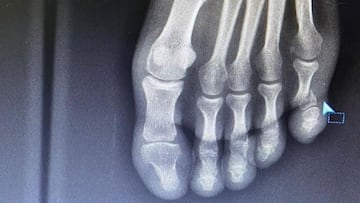

El ciclista colombiano Rigoberto Urán (EF Education Nippo) se fracturó el dedo meñique del pie izquierdo al tropezar con su cama, informó este lunes el corredor en redes sociales. "Me fracturé el dedo pequeño del pie con la punta de la cama", escribió Urán en Instagram, y agregó: "Otra fractura para mi palmarés, pero nada nos frena". La publicación está acompañada de una radiografía en la que se aprecia la lesión.